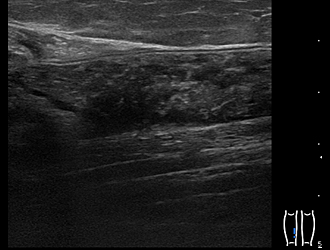

肩板部分断裂

下腿肉離れ

変形性膝関節症 関節水腫

手関節部ガングリオン

打撲後 皮下血腫

肘離断性骨軟骨炎

左肋骨骨折